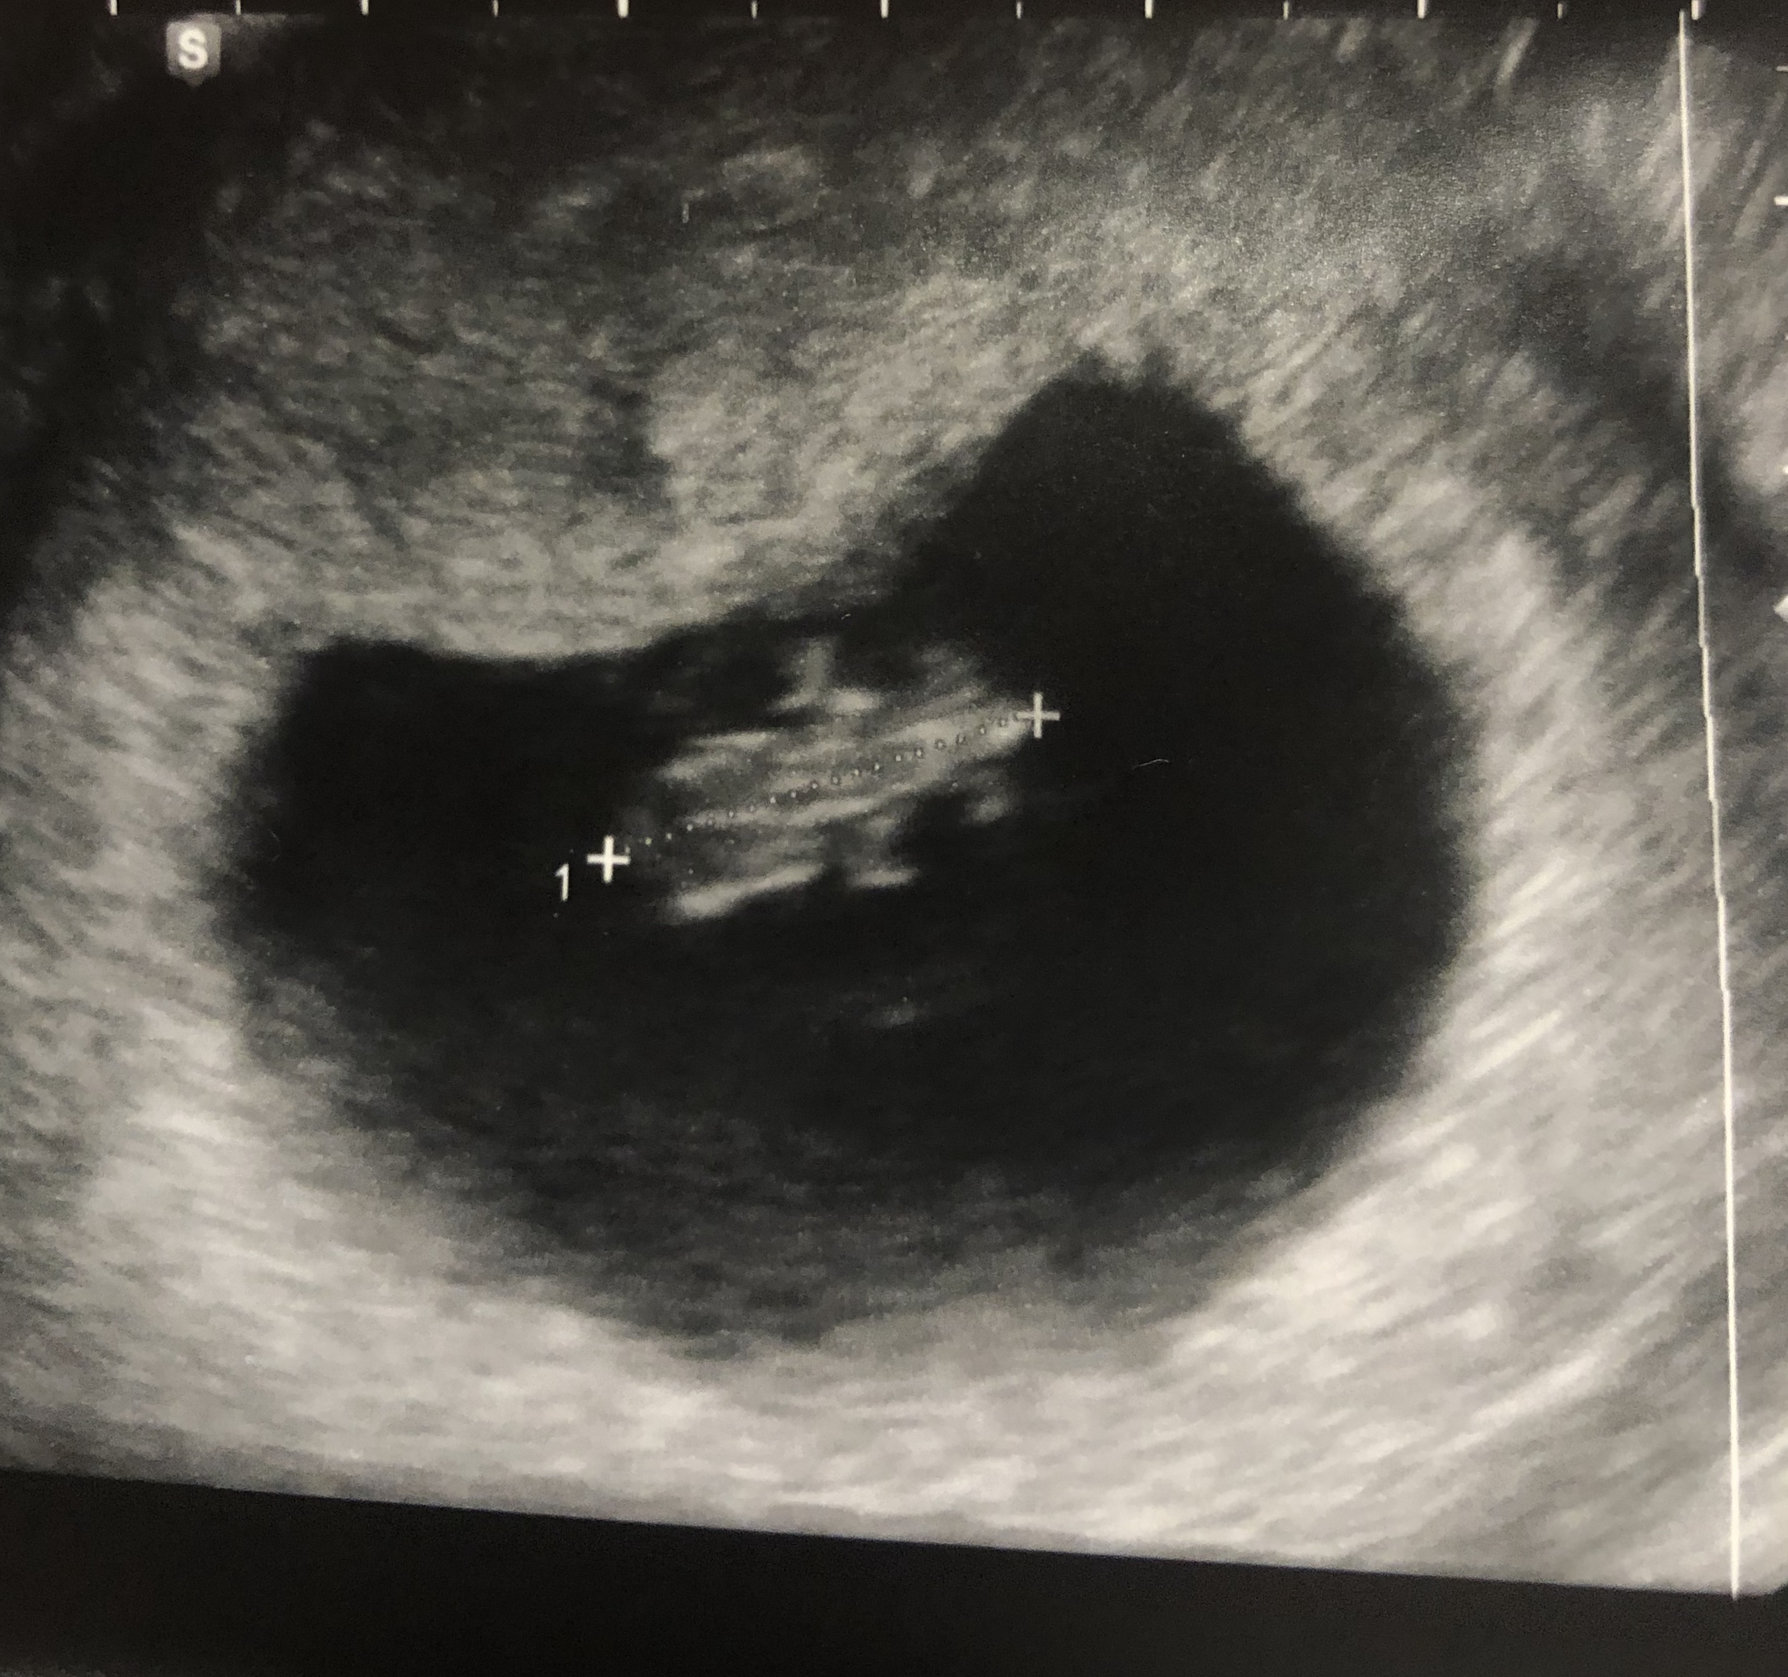

6 weeks, 4 days, and we saw his/her heartbeat!!!! 116 bpm, which doc said is on the slow side, but normal for having a brand new heart. Already in love, and praying we welcome this baby in February